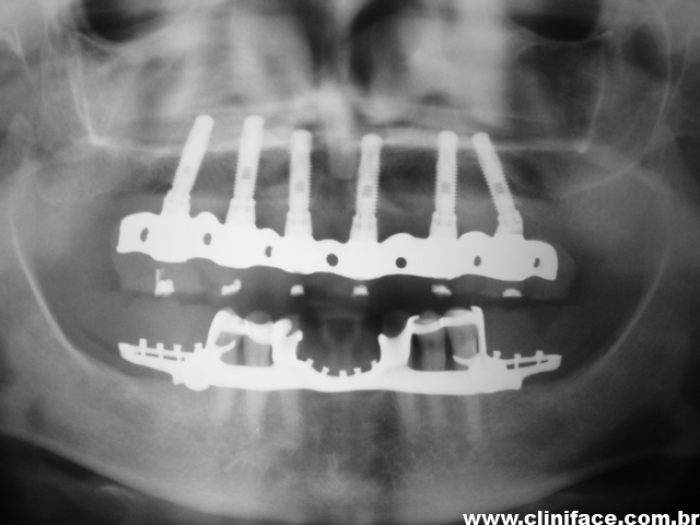

Raio X inicial

Raio X dos Implantes Instalados